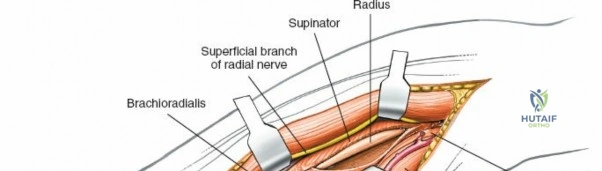

Incise the deep fascia of the forearm in line with the skin incision. The initial goal is to identify the medial border of the brachioradialis as it courses down the forearm. It is a common pitfall to search for this border too far laterally. At the level of the elbow, the brachioradialis is expansive and extends almost halfway across the anterior forearm. It is surprisingly easy to mistake the plane between the brachioradialis and the extensor carpi radialis longus for the correct intermuscular plane.

To confirm the correct plane, look for the superficial branch of the radial nerve. This sensory nerve runs on the undersurface of the brachioradialis muscle. Once the true medial edge of the brachioradialis is found, develop the plane between it and the pronator teres (proximally) or the flexor carpi radialis (distally). Retract the brachioradialis laterally, taking care to keep the superficial radial nerve attached to its undersurface to protect it from traction injury.

The proximal radius is draped by the supinator muscle. The PIN passes directly through the belly of the supinator. To protect the nerve, the forearm must be fully supinated. Supination dynamically rotates the radius, carrying the insertion of the supinator anteriorly and simultaneously displacing the PIN laterally and posteriorly, safely away from the surgical field.

With the forearm fully supinated, identify the broad insertion of the supinator on the anterior aspect of the radius. Incise the supinator directly along the line of its insertion onto the bone. It is critical to detach the muscle by dividing its insertion sharply at the bone, rather than splitting the muscle belly, which would risk cutting the PIN.

Proceed with strict subperiosteal dissection, elevating the supinator laterally off the bone. This is one of the rare instances in orthopedic surgery where the safety gained by staying in a subperiosteal plane completely outweighs the theoretical vascular damage to the bone caused by periosteal stripping. The elevated supinator muscle belly now acts as a protective cushion for the PIN.